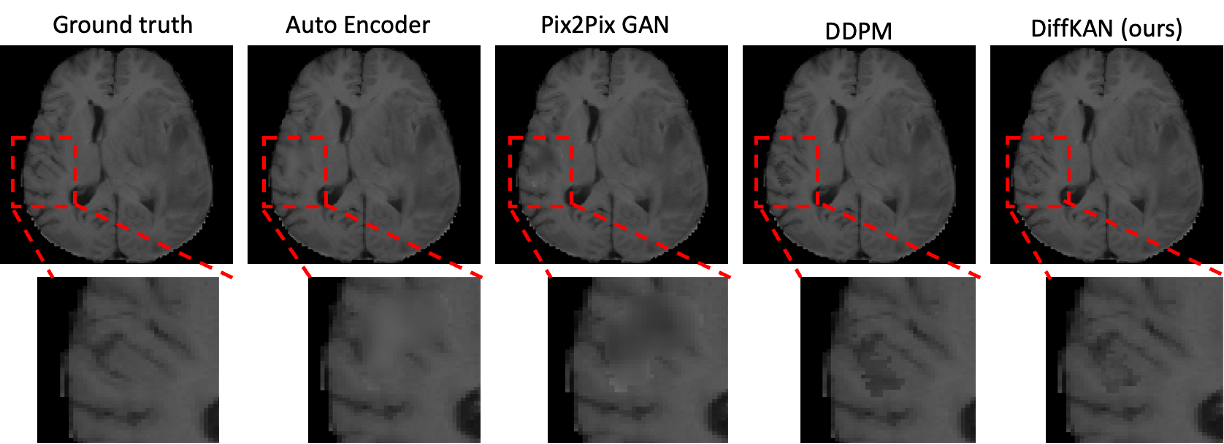

Results. To complement the qualitative evaluations, we conducted comprehensive quantitative analyses to objectively assess the performance of DiffKAN-inpainting against the state-of-the-art baseline methods, such as, AutoEncoder [10], Pix2Pix GAN [11] and DDPM [12].

In Figure 2, we present a representative showcase in brain inpainting from the BraTS dataset. The results clearly demonstrate that our approach generates more realistic and intricate brain tissue structures compared to traditional U-Net-based models. The result generated by the Auto Encoder and Pix2Pix2 GAN is blurry and failed to delineate the complicated brain gyrus. Specifically, our results exhibit fewer minor disparities in the brain cerebral gyrus compared to other methods.

Refer to caption

Fig. 2: Showcase of the inpainted brain images by our proposed DiffKAN-Inapinting method.